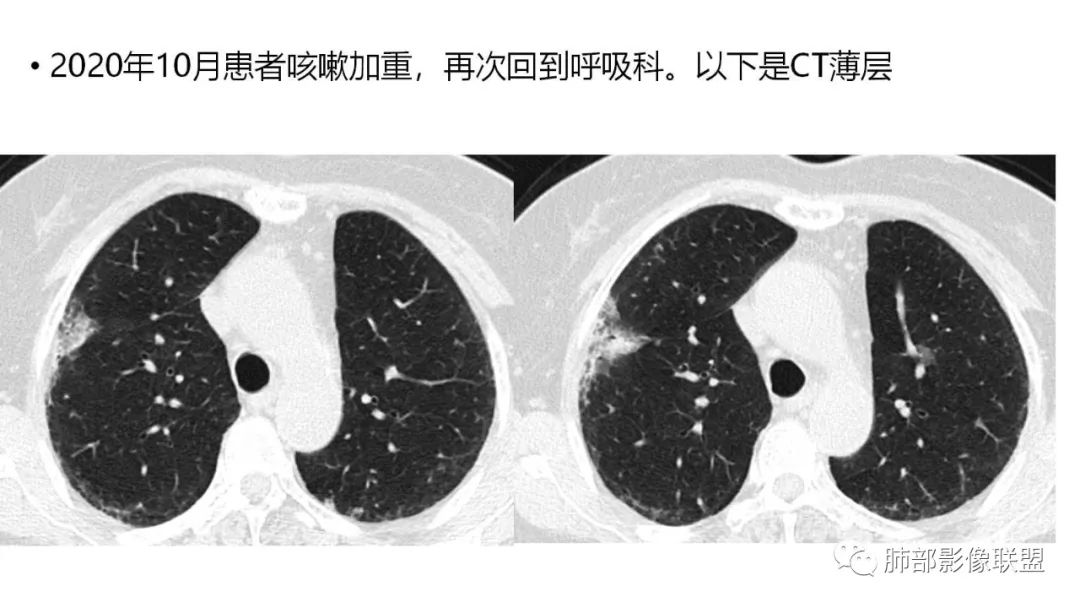

二、肺炎型

2、病灶常有一个主病灶,常位于下肺。后沿气道播散为多发病灶。

3、重力作用,叠瓦征。近叶间裂因重力效应,呈膨隆改变。

4、增强后不均匀强化,存在低强化区呈弱强化或无强化,因此可见“血管造影征。”血管毛糙与肺炎有统计学差异。

5、支气管粗细不均,呈“枯树枝征”,但与肺炎这一点鉴别不具有统计学差异。可发生支气管扩张

6、空腔形成,部分蜂窝状改变。

8、斑片常伴有结节,边缘清楚GGO或欠清楚。

9.粘液腺癌的变化规律:结节缓慢发展而来,向周围播散形成斑片后可快速进展,有时支气管镜后或粘液排出后局部可形成好转的假象。病灶可沿肺泡和支气管播散。

三、本例是一个误诊多年的病例,给我们很多启示:

2.粘液腺癌易伪装成肺炎的形态,尤其是当患者本身具有免疫色彩的时候,易误诊为间质性肺炎,或肺部感染。若治疗无效,取得病理很重要。

4.回到本例,左下肺病变两次好转,均未经过肿瘤治疗,第一次是支气管镜后,第二次是当其他病变都在进展的情况下,左下肺病变范围反而缩小趋于浅淡。